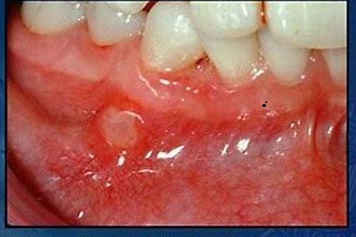

درمان آفت و زخمهای دهان